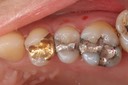

Alan Chinn #2 & 5 pre-op